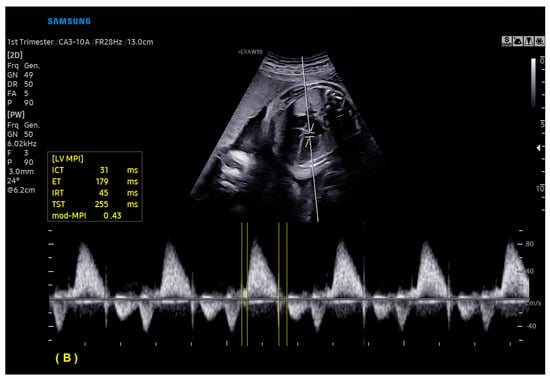

With ML, the ultrasound machine is able to automatically obtain cardiac measurements based on the identification of anatomical cardiac structures, reducing the scan time and inter-observer measurement variation. In this scenario, not only anatomical, but also functional parameters (such as the myocardial performance index) can be automatically measured. With the advances in AI, this technology has been increasingly added to ultrasound devices, such as obstetric ultrasound, and is applicable to three areas: structure identification, automatic measurements, and the classification of diagnosis. AI software (Heart Assist and MPI+—Samsung Healthcare, Gangwon, South Korea) can identify the fetal heart structures and perform automatic biometric and the right and left myocardial performance index measurements, respectively (Figure 12 and Figure 13) [42,43,44].

Artificial Intelligence (MPI+) The ultrasound machine is able to select Doppler images of the ventricular inflow and outflow tracts, identify valve clicks, and perform cardiac cycle time measurements. (A) Modified myocardial performance index (mod-MPI) was automatically calculated for the right (A) and left (B) ventricles of a fetus in the first trimester of pregnancy. LV: left ventricle; RV: right ventricle; ET: ejection time; ICT: isovolumetric contraction time; IRT: isovolumetric relaxation time.